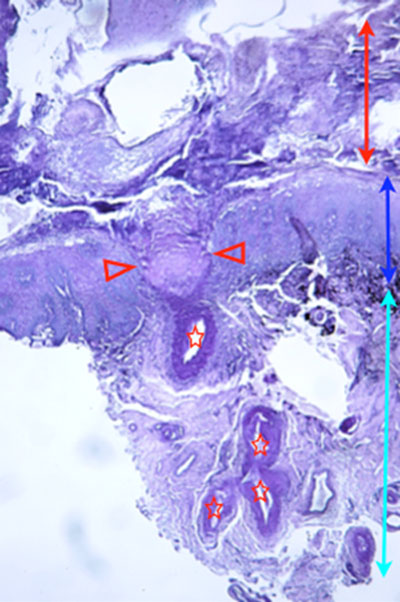

A l’examen histologique, on note la présence d’une ulcération épidermique focale, recouverte d’un enduit pustulo-croûteux pluristratifié fibrino-leucocytaire (Photo 3). Dans le plancher de cet ulcère, se trouve une artériole dont la paroi est rompue (Photos 4 & 5). Dans le derme, sous l’ulcère épidermique, on trouve de multiples silhouettes anormales de vaisseaux à paroi musculeuse de taille petite à moyenne : leur contour est irrégulier et leur pourtour inflammatoire (Photo 6). Leur paroi est épaissie : le tissu conjonctif sous-endothélial peut être anormalement proéminent et épaissi. On y trouve des myofibroblastes et des fibres de collagène. La media de ces artérioles est hyperplasique (hyperplasie musculaire lisse). L’épaississement sous-endothélial donne des images focales d’artérite oblitérante (Photos 7 & 8). On remarque très régulièrement un infiltrat inflammatoire à prédominance lympho-plasmocytaire, s’immisçant dans l’adventice et la media de ces vaisseaux (Photos 6,7,8). Ces structures des vaisseaux artériolaires n’étant habituellement le siège d’aucune diapédèse, la présence de cellules inflammatoires y est considérée comme anormale et signe des lésions d’artérite.

Photo 3 (réaction au PAS – X 25) : l’épiderme apparaît focalement ulcéré.

Sous l’ulcère, des vaisseaux dermiques anormaux sont présents, l’un forme le plancher de l’ulcère.

Légendes de la Photo 3 :

- Pointes de flèches rouges = délimitation de l’ulcère épidermique.

- Etoiles rouges = vaisseaux sanguins dermiques sous l’ulcère épidermique.

- Flèche double rouge = croûtes séro-cellulaires stratifiées à la surface de l’épiderme.

- Flèche double bleue = épaisseur épidermique.

- Flèche double turquoise = épaisseur dermique.